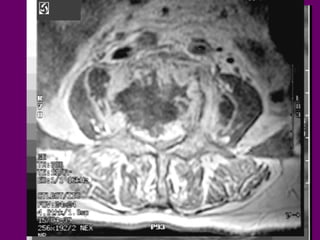

Xaâm laán coät soáng töø ung thö

phoåi

Di caên coät

soáng